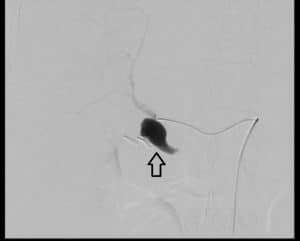

Afterwards, she underwent a celiac angiography. Access was made through the right common femoral artery with cannulation of the coeliac axis and hepatic artery. It redemonstrated a large, narrow neck pseudoaneurysm arising from the right hepatic artery just before the trifurcation (figure 2).

Figure 2: Angiography pre coiling